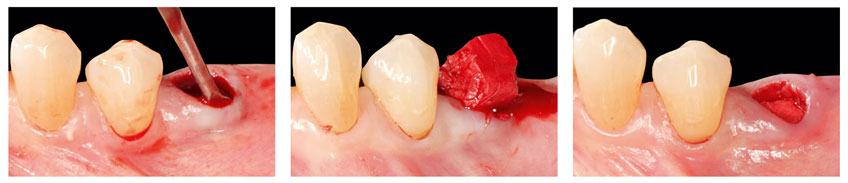

Applikation von OSSIX™ Bone in eine Extraktionsalveole ohne Lappenpräparation: Nach der Zahnextraktion (li) wird OB mit Defektblut getränkt (Mi) und vorsichtig bis zum krestalen Level in die Alveole eingebracht (re). Mit freundlicher Genehmigung von Dr. Fred Silva, USA.